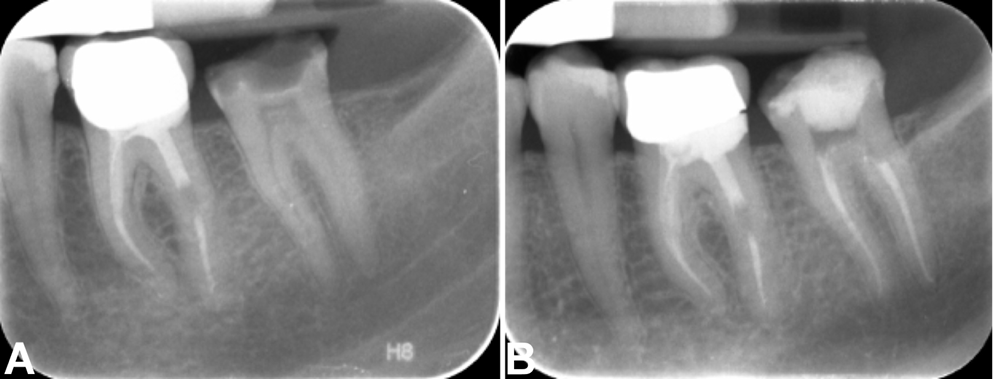

Group II: single cone obturation

Following master cone verification, the premixed Cerafill RCS® sealer was injected into the root canal using flexible syringe injection tips provided by the manufacturer. Before injection, the applicator tip was adjusted to 5–6 mm short of the working length using a rubber stop and calibrated with the Endo-Block (Dentsply Maillefer). The flexible syringe injection tip was then placed into the canal until the rubber stop was reached. The Cerafill RCS® sealer was injected by gently pressing the syringe plunger while withdrawing the tip until the sealer was visible at the root canal orifice. The tip of the master cone was then coated with the bioceramic sealer and inserted carefully to the desired working length. Excess gutta-percha was removed using a heat carrier tip set at 180°C, and the material was condensed to 1 mm below the canal orifice level (Figure 3).